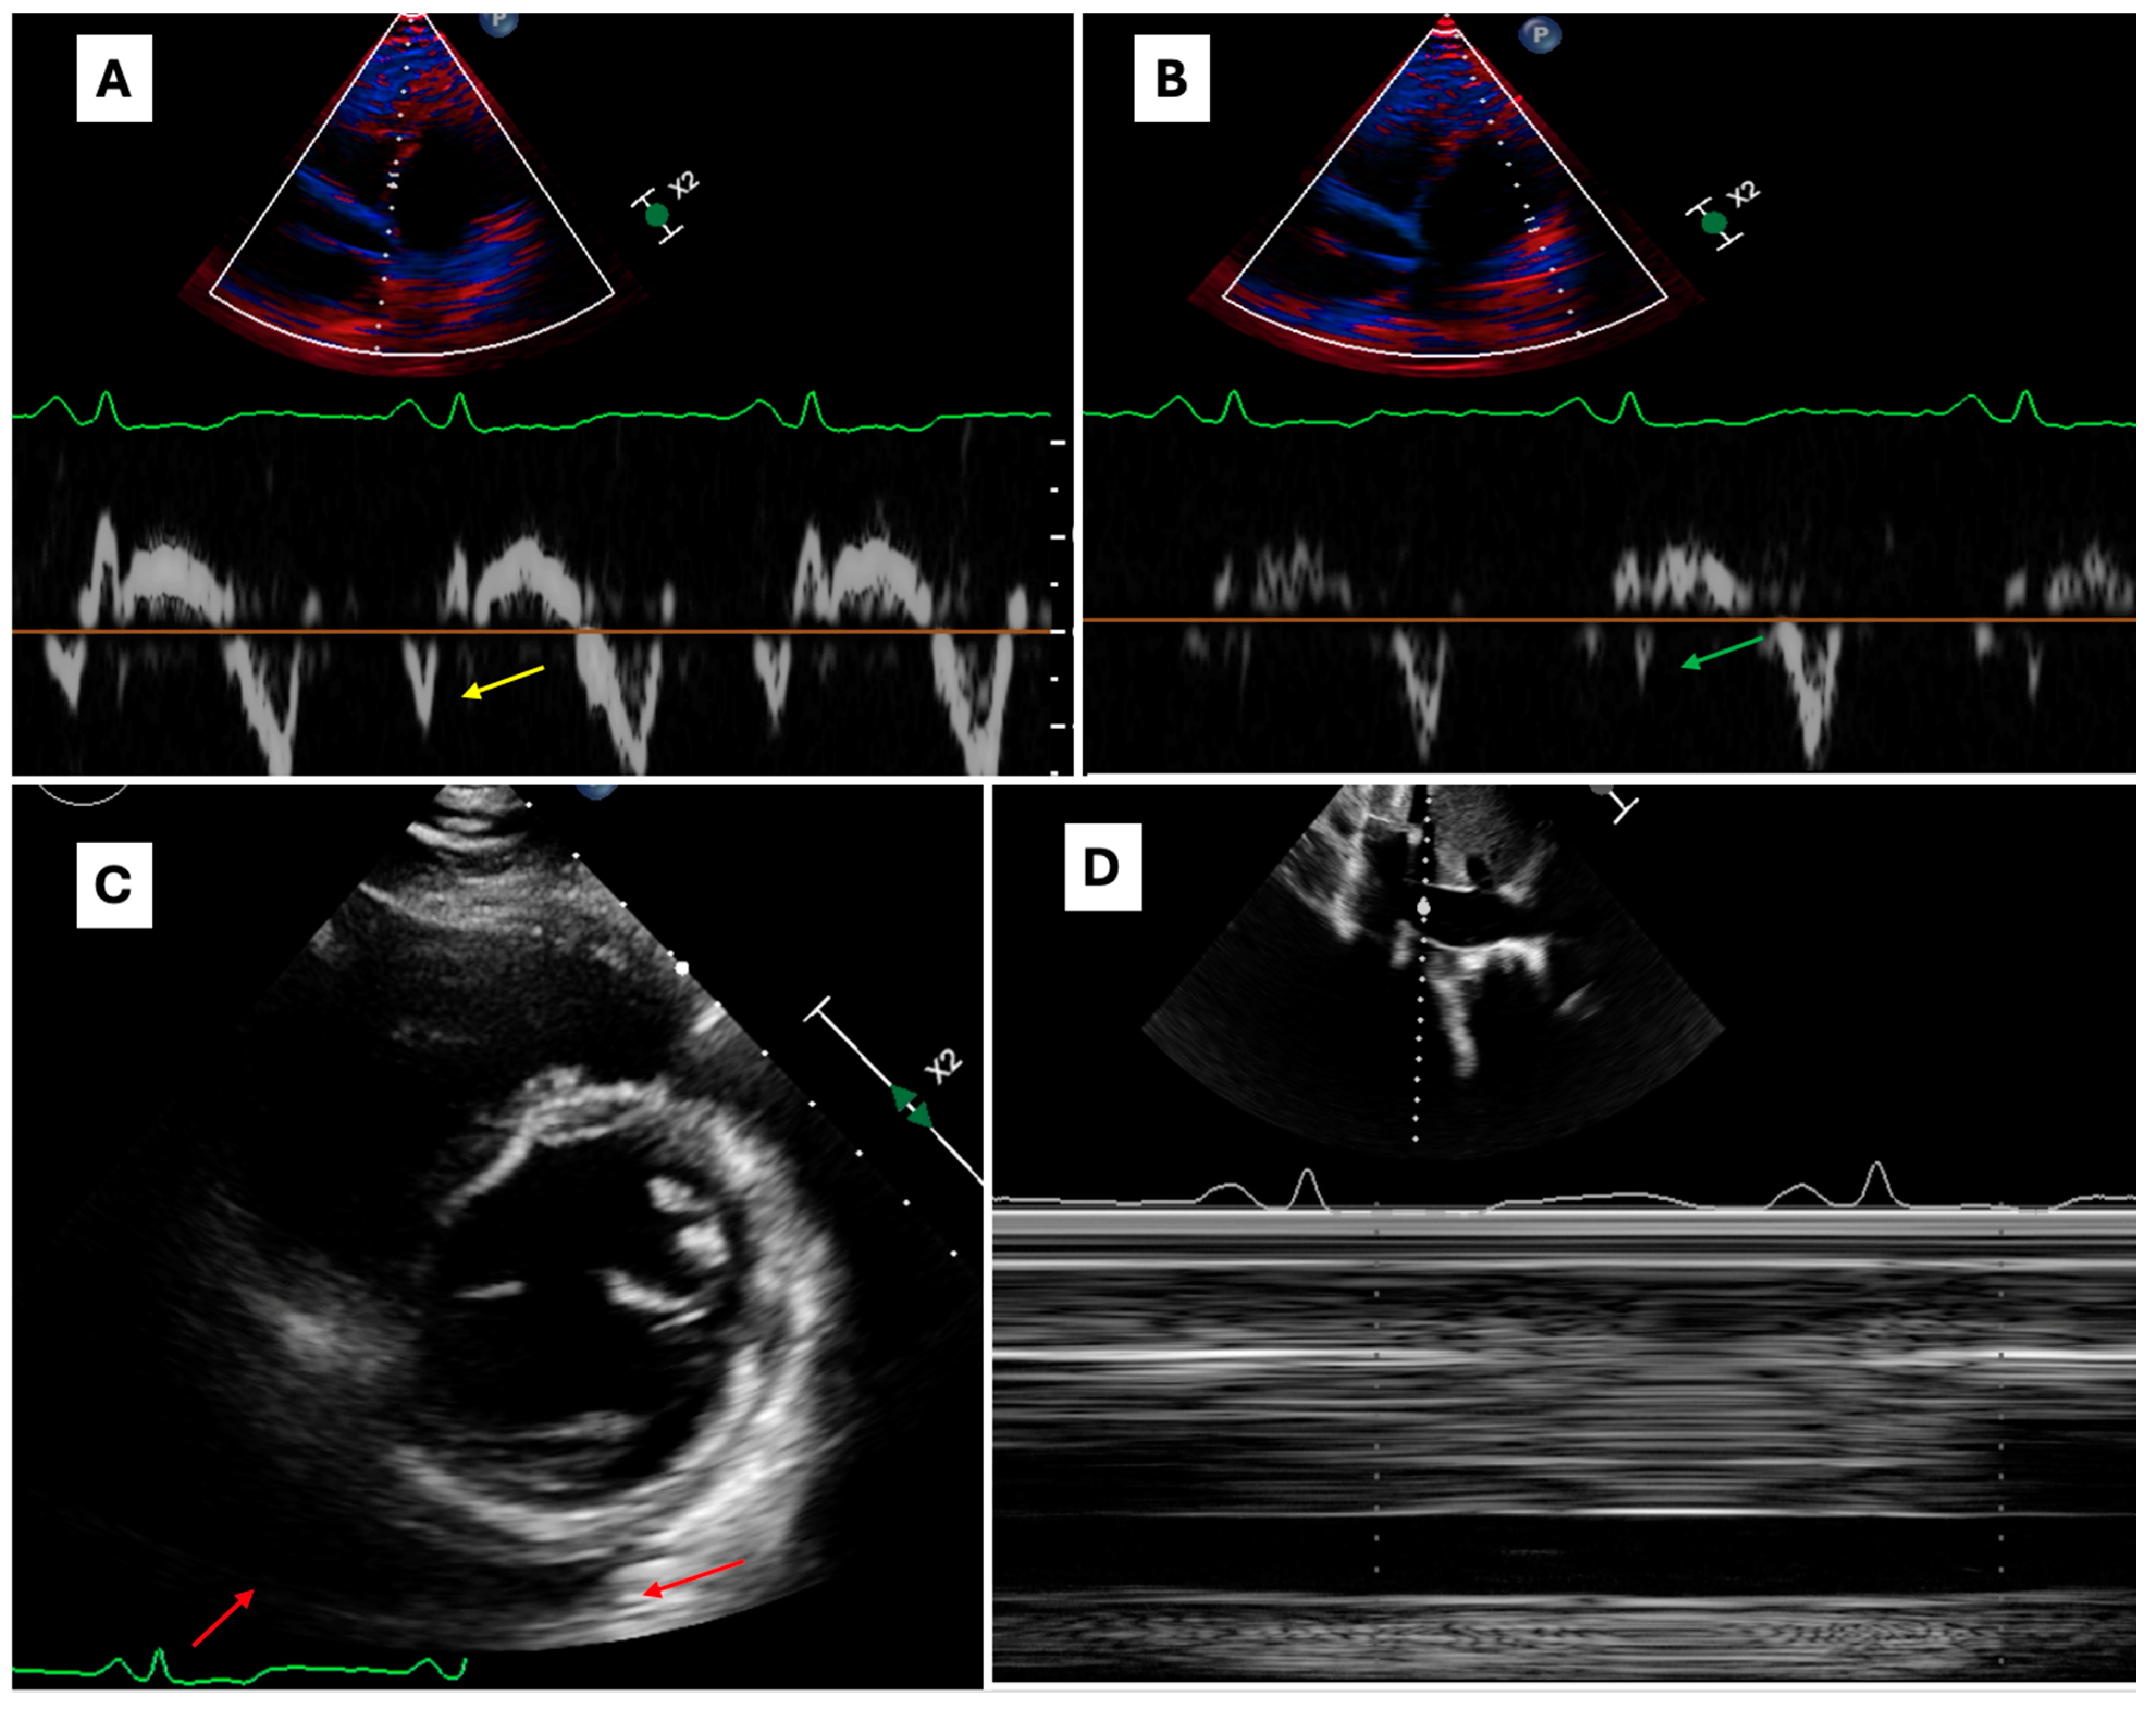

3.4. Constrictive Pericarditis Cases